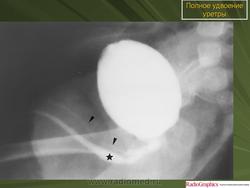

5. Удвоение уретры.